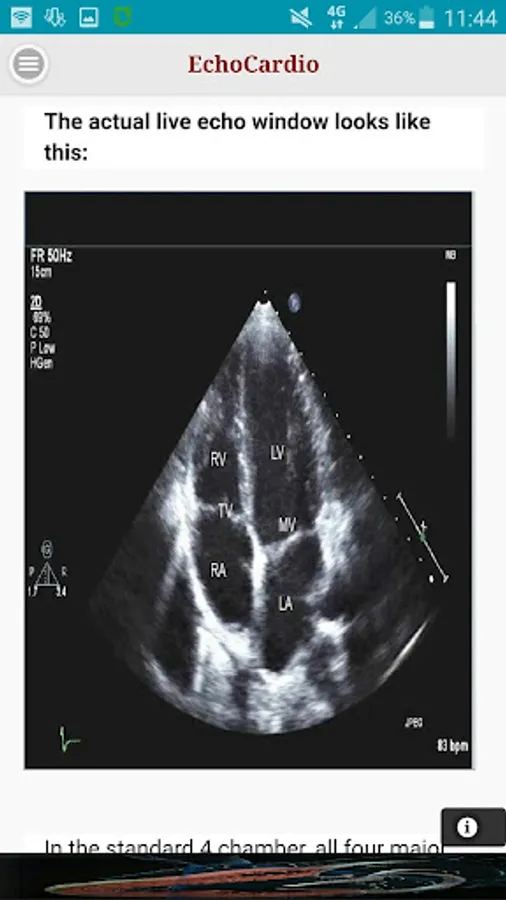

Transthoracic echocardiography (TTE) is the most commonly performed cardiac ultrasound examination. A high quality transthoracic echocardiogram can be performed quickly at the bedside and has the potential to comprehensively evaluate left and right ventricular systolic and diastolic function, regional wall motion, valvular heart disease, and diseases of the pericardium.

Apical